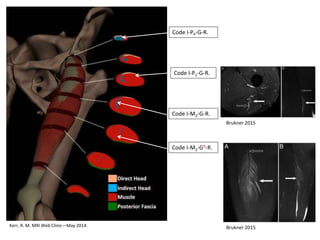

Examples of Indirect RF Injuries

Around the Proximal MTJ

Kerr, R. M. MRI Web Clinic—May 2014.

Code I-PP-G-R.

Code I-P1-G-R.

Code I-M2-G-R.

Code I-M2-GR-R.

Brukner 2015